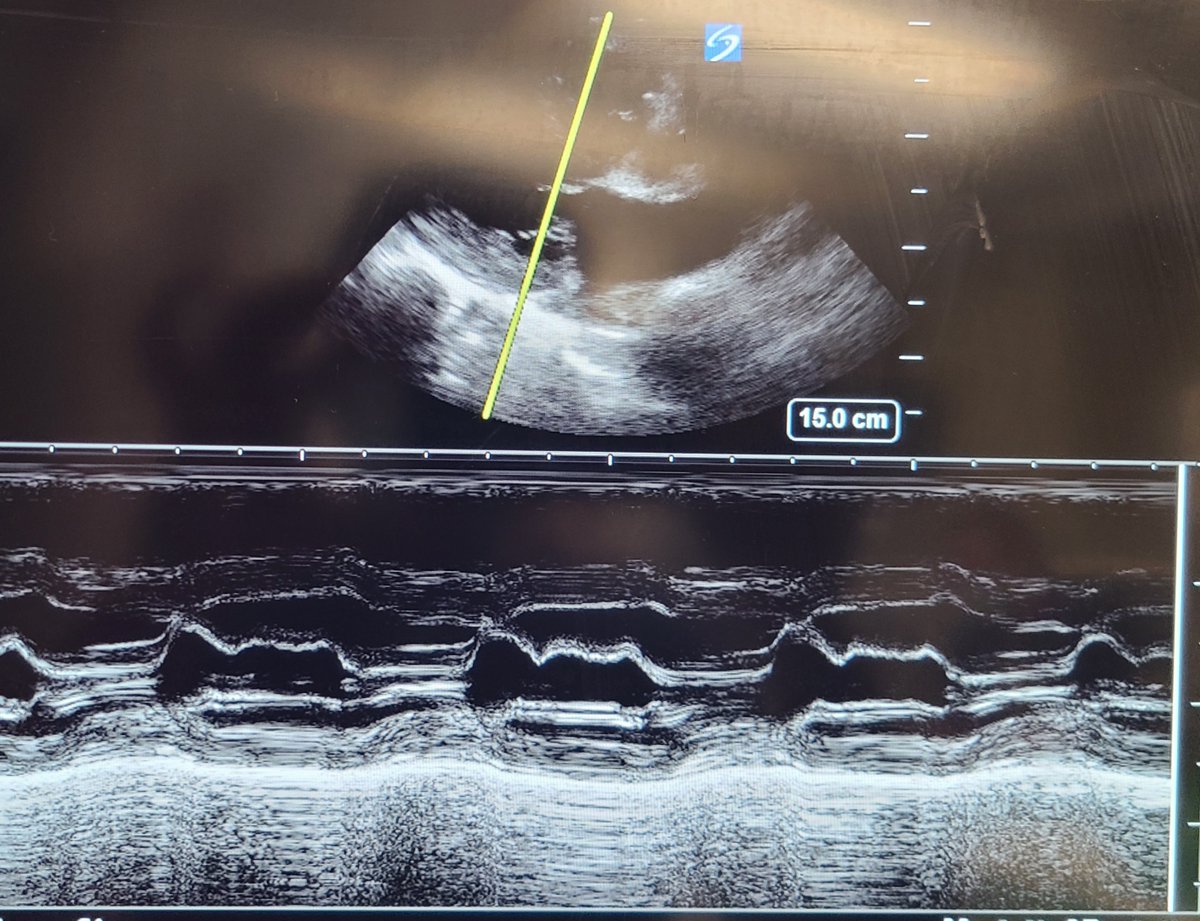

Bedside echo performed in MICU:

Parasternal long axis

Echocardiogram demonstrates preserved EF without evidence of RV pressure overload, no overt pericardial or pleural effusion but confirms low cardiac output driven by bradycardia (CO calculated 3L/min)